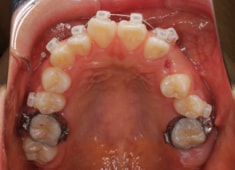

治療開始時